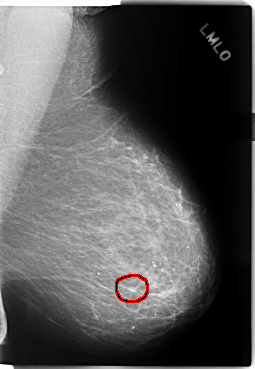

C_0205_1.LEFT_MLO

LEFT_MLO LINES 5896 PIXELS_PER_LINE 4072 BITS_PER_PIXEL 12 RESOLUTION 50 OVERLAY

FILE: C_0205_1.LEFT_MLO.OVERLAY

TOTAL_ABNORMALITIES 1

ABNORMALITY 1

LESION_TYPE MASS SHAPE IRREGULAR MARGINS ILL_DEFINED

ASSESSMENT 4

SUBTLETY 2

PATHOLOGY MALIGNANT

TOTAL_OUTLINES 1

BOUNDARY